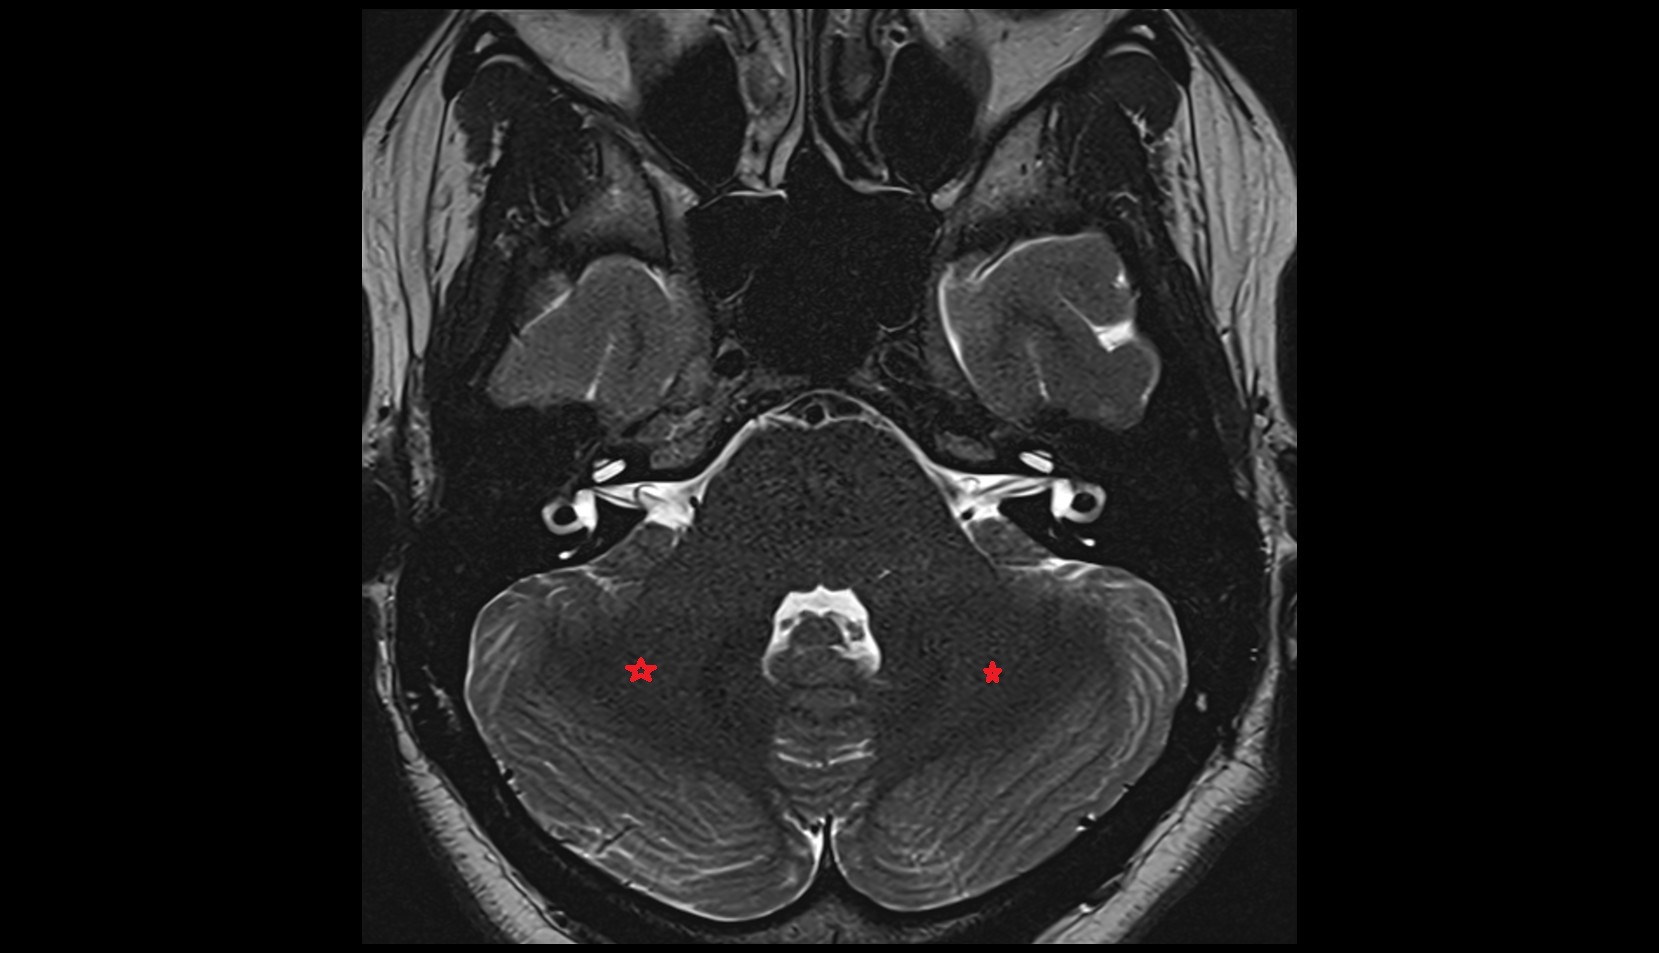

- Crus I of ansiform lobule of cerebellum

- Crus II of ansiform lobule of cerebellum

- Paramedian lobule (HVII) of cerebellum

- Simple lobule (HVI) of cerebellum

- Anterior quadrangular lobule (HV) of cerebellum

- Anterior quadrangular lobule (HlV) of cerebellum

- Biventral lobule (HVIII) of cerebellum

- Cerebellar tonsil (H IX)